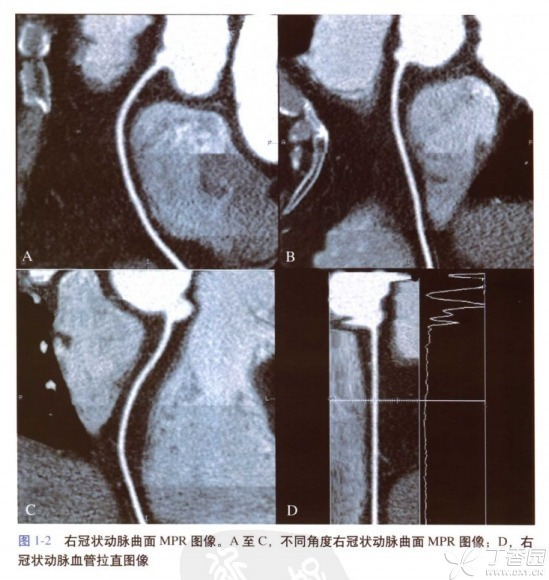

CPR可以观察管腔结构的腔壁病变(如斑块、狭窄等),也可以观察管状结构与周围结构的位置关系,但CPR所显示的不是正常的解剖结构和关系(它是把管状结构拉直了看,例如图二的冠脉拉直图像),同时需要多个角度曲面重建以完整评价病变。